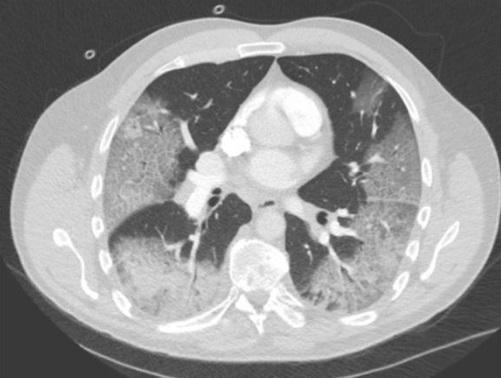

¿Cuál es el diagnóstico?

A

Consolidación vidrio esmerilado y empedrado loco.